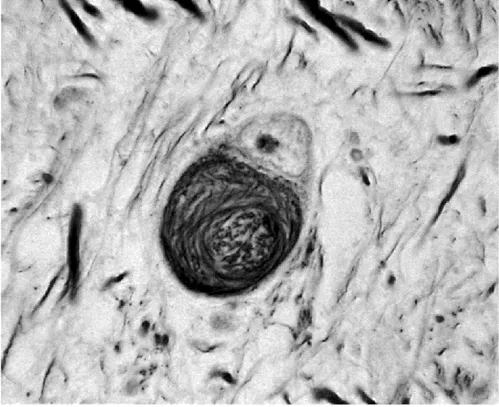

Nowhere are these discrepancies more evident than in cases of progressive supranuclear palsy (PSP). One of the problems in establishing clinicopathological correlations in PSP is the lack of consensus as to the pathological criteria for the diagnosis. Certain features, however, are predictable. The substantia nigra shows severe pigment depletion, as does the locus ceruleus. Neuronal loss is found in the substantia nigra, subthalamus, and globus pallidus. Neurofibrillary tangles can be identified in the cerebral cortex, caudate, putamen, globus pallidus, subthalamus, and brain stem (Figure 26). Accompanying the neurofibrillary tangles are neuropil threads (silverand tau-positive). Typically, changes are found in the regions associated with vertical gaze, including the rostral interstitial nucleus of the medial longitudinal fasciculus and the interstitial nucleus of Cajal Tau is a microtubule-associated protein which is closely involved in neuronal axonal transport. Frequent tau-positive inclusions are found in PSP and corticobasal degeneration

Figure 26 Progressive supranuclear palsy: subthalamic neurons showing neurofibrillary tangle (Bielschowsky silver impregnation)